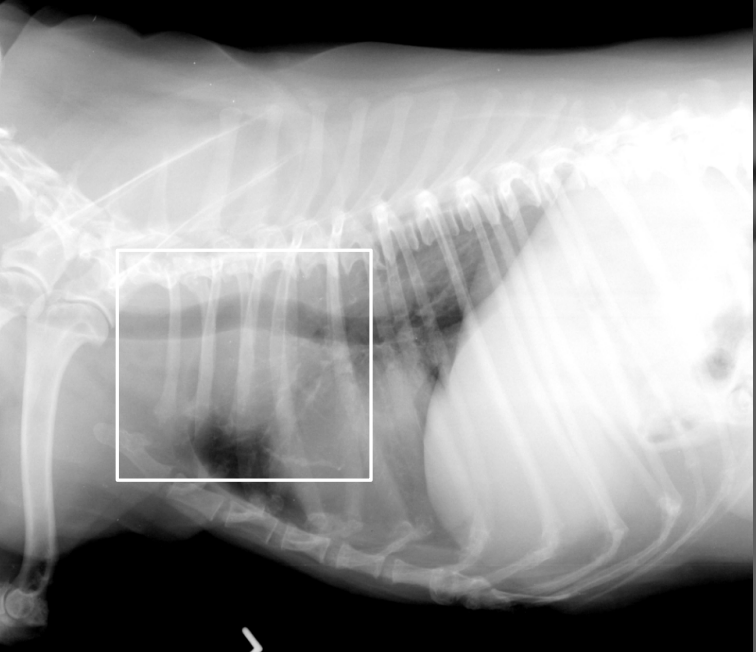

What is shown in these images?

segmented megaesophagus due to vascular ring anomaly/persistent right aortic arch